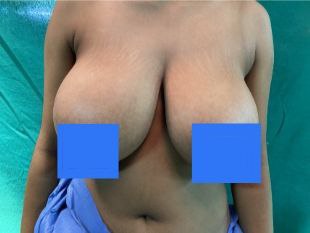

Cosmetic

BREAST REDUCTION